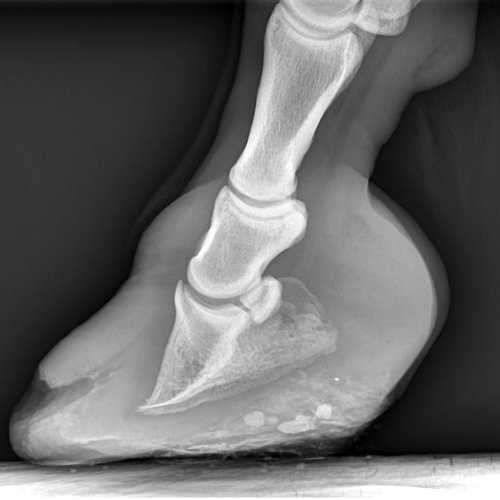

Radiography

The very latest in equine digital radiography (X-rays) with images arriving within seconds for a speedy diagnosis.